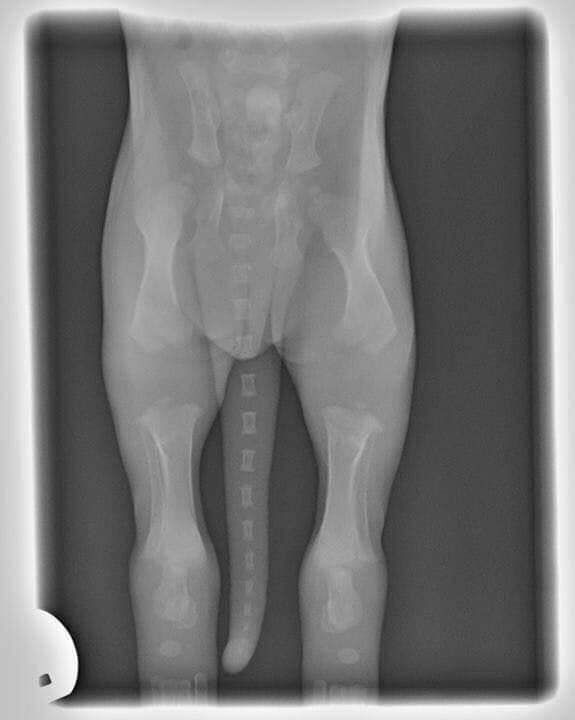

Dies ist ein Röntgenbild eines 2 Wochen alten Welpen.

Schauen Sie sich an, wie weit die Knochen wachsen müssen, bevor sie zu einem richtigen Knochengelenk werden! Aus diesem Grund sollten Sie Welpen niemals springen, Treppen rauf/absteigen, zu viel Sport treiben oder trainieren lassen. Wenn man in jungen Jahren zu viel Impact-Aktivität ausführt, kann dies später im Leben oder sogar in jungen Jahren zu ernsthaften Problemen führen, da Hüftdysplasie und andere orthopädische Erkrankungen bei Welpen zunehmen!

Denken Sie daran, dass die Welpen Regel für jeden Monat die Aktivität um 5 Minuten erhöht!

Zum Beispiel: Ein 8 Wochen alter Welpe braucht nur 10 Minuten Bewegung am Tag, ein 6 Monate alter Hund braucht nur 30 Minuten Bewegung am Tag!!